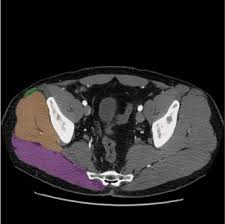

Presentation1 Pptx Radiological Anatomy Of The Thigh And Leg

Presentation1 Pptx Radiological Anatomy Of The Thigh And Leg from cdn.slidesharecdn.com